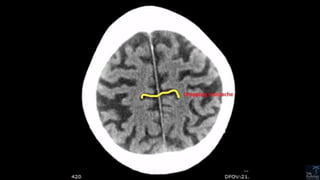

The central sulcus-The sigmoid hook